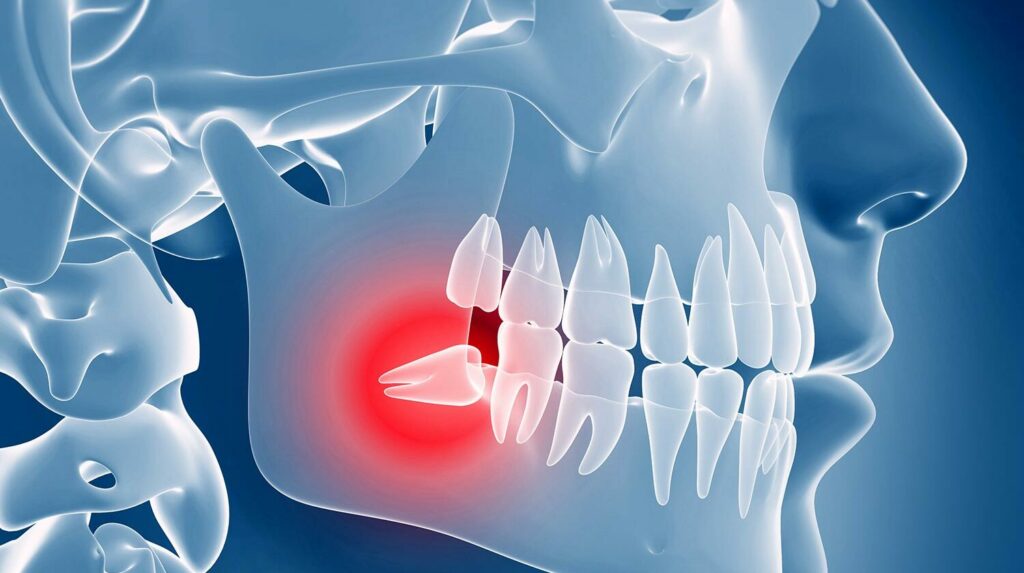

Wisdom teeth can cause problems if there is insufficient space for them to emerge or if they erupt in the wrong position.

Your wisdom teeth may also be impacted, meaning they are trapped in your jaw or under your gums. Impacted teeth are difficult to clean, can trap food, and may lead to the following issues:

- The gums overlying impacted wisdom teeth may become infected and swollen, causing a painful condition called pericoronitis.

- They can cause decay in the second molar in front.

- Teeth in front may become crowded.

- They can develop into cysts, which may damage neighboring teeth.

Your dentist may also recommend removal of wisdom teeth as part of orthodontic treatment or other dental procedures. Wisdom teeth may require surgical removal if any of the following symptoms are present:

- An x-ray will be taken to check the position of the wisdom tooth.